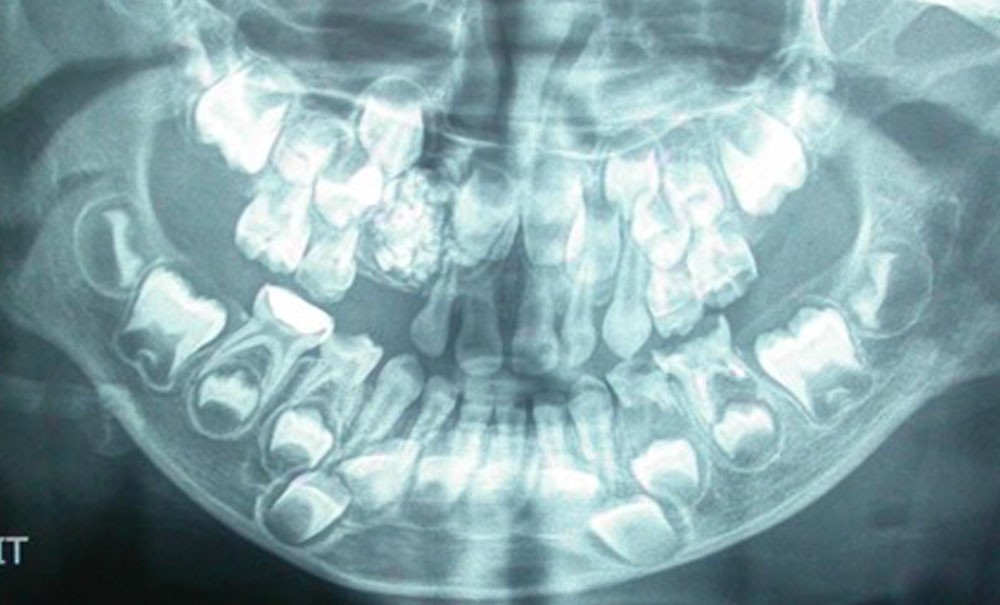

Les odontomes sont des tumeurs odontogéniques bénignes de type hamartomateux. Selon Broca, ils sont formés par une croissance excessive de l’ensemble des tissus dentaires compromettant parfois, lorsqu’ils se développent dans leurs trajets, l’éruption normale des dents.

– l’odontome composé, correspondant à une masse dont l’anatomie ressemble à une dent ou à un ensemble de petites dents rudimentaires assemblées en amas, le plus souvent dans la région antérieure du maxillaire ;

– l’odontome complexe, décrit comme une masse anarchique de matériaux dentaire, retrouvé plus fréquemment dans les régions molaires, prémolaires.

La découverte est souvent fortuite, à l’occasion d’un examen radiologique de routine ou à la suite de l’absence d’une dent sur l’arcade. Dans certains cas, une symptomatologie, de type douleurs, infections…